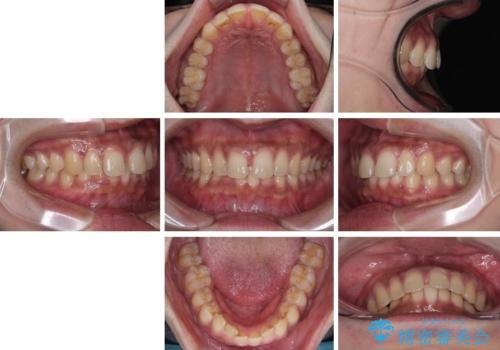

- 上の前歯の正中離開(すきっ歯)と、下顎前歯部の叢生(デコボコ)を主訴に来院された患者様の症例です。

「目立ちにくい装置で治療したい」とのご希望があり、透明のマウスピース矯正であるインビザラインを用いて矯正治療を行いました。

正中離開は舌の癖(舌突出癖)がある場合、後戻りしやすい傾向があります。

そのため当院では矯正治療と並行して、正しい舌の位置・飲み込み方・呼吸の仕方などをトレーニングする

**MFT(口腔筋機能療法)**を実施し、治療後の安定性を高めています。